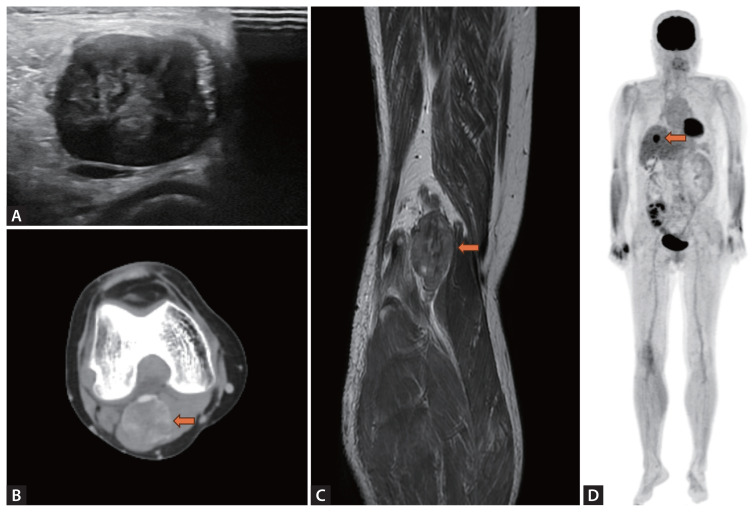

肾移植患者腘静脉平滑肌肉瘤表现为单侧腿部水肿。

Leiomyosarcoma at popliteal vein presented as unilateral leg edema in a patient with kidney transplantation.